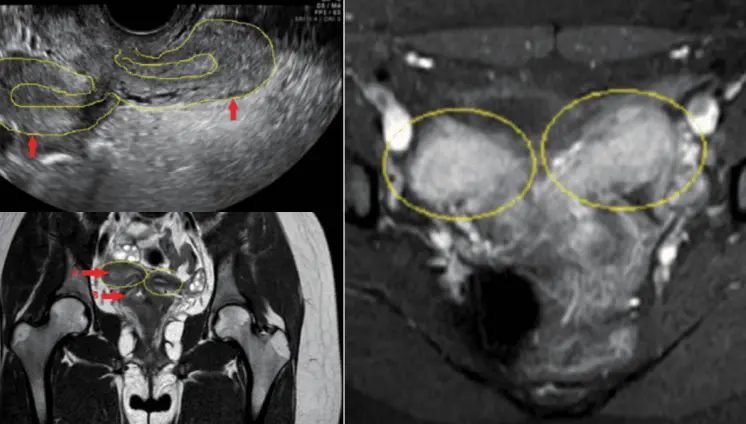

Dolor pélvico agudo y sangrado en adolescente: Resonancia revela útero doble y agenesia renal ipsilateral